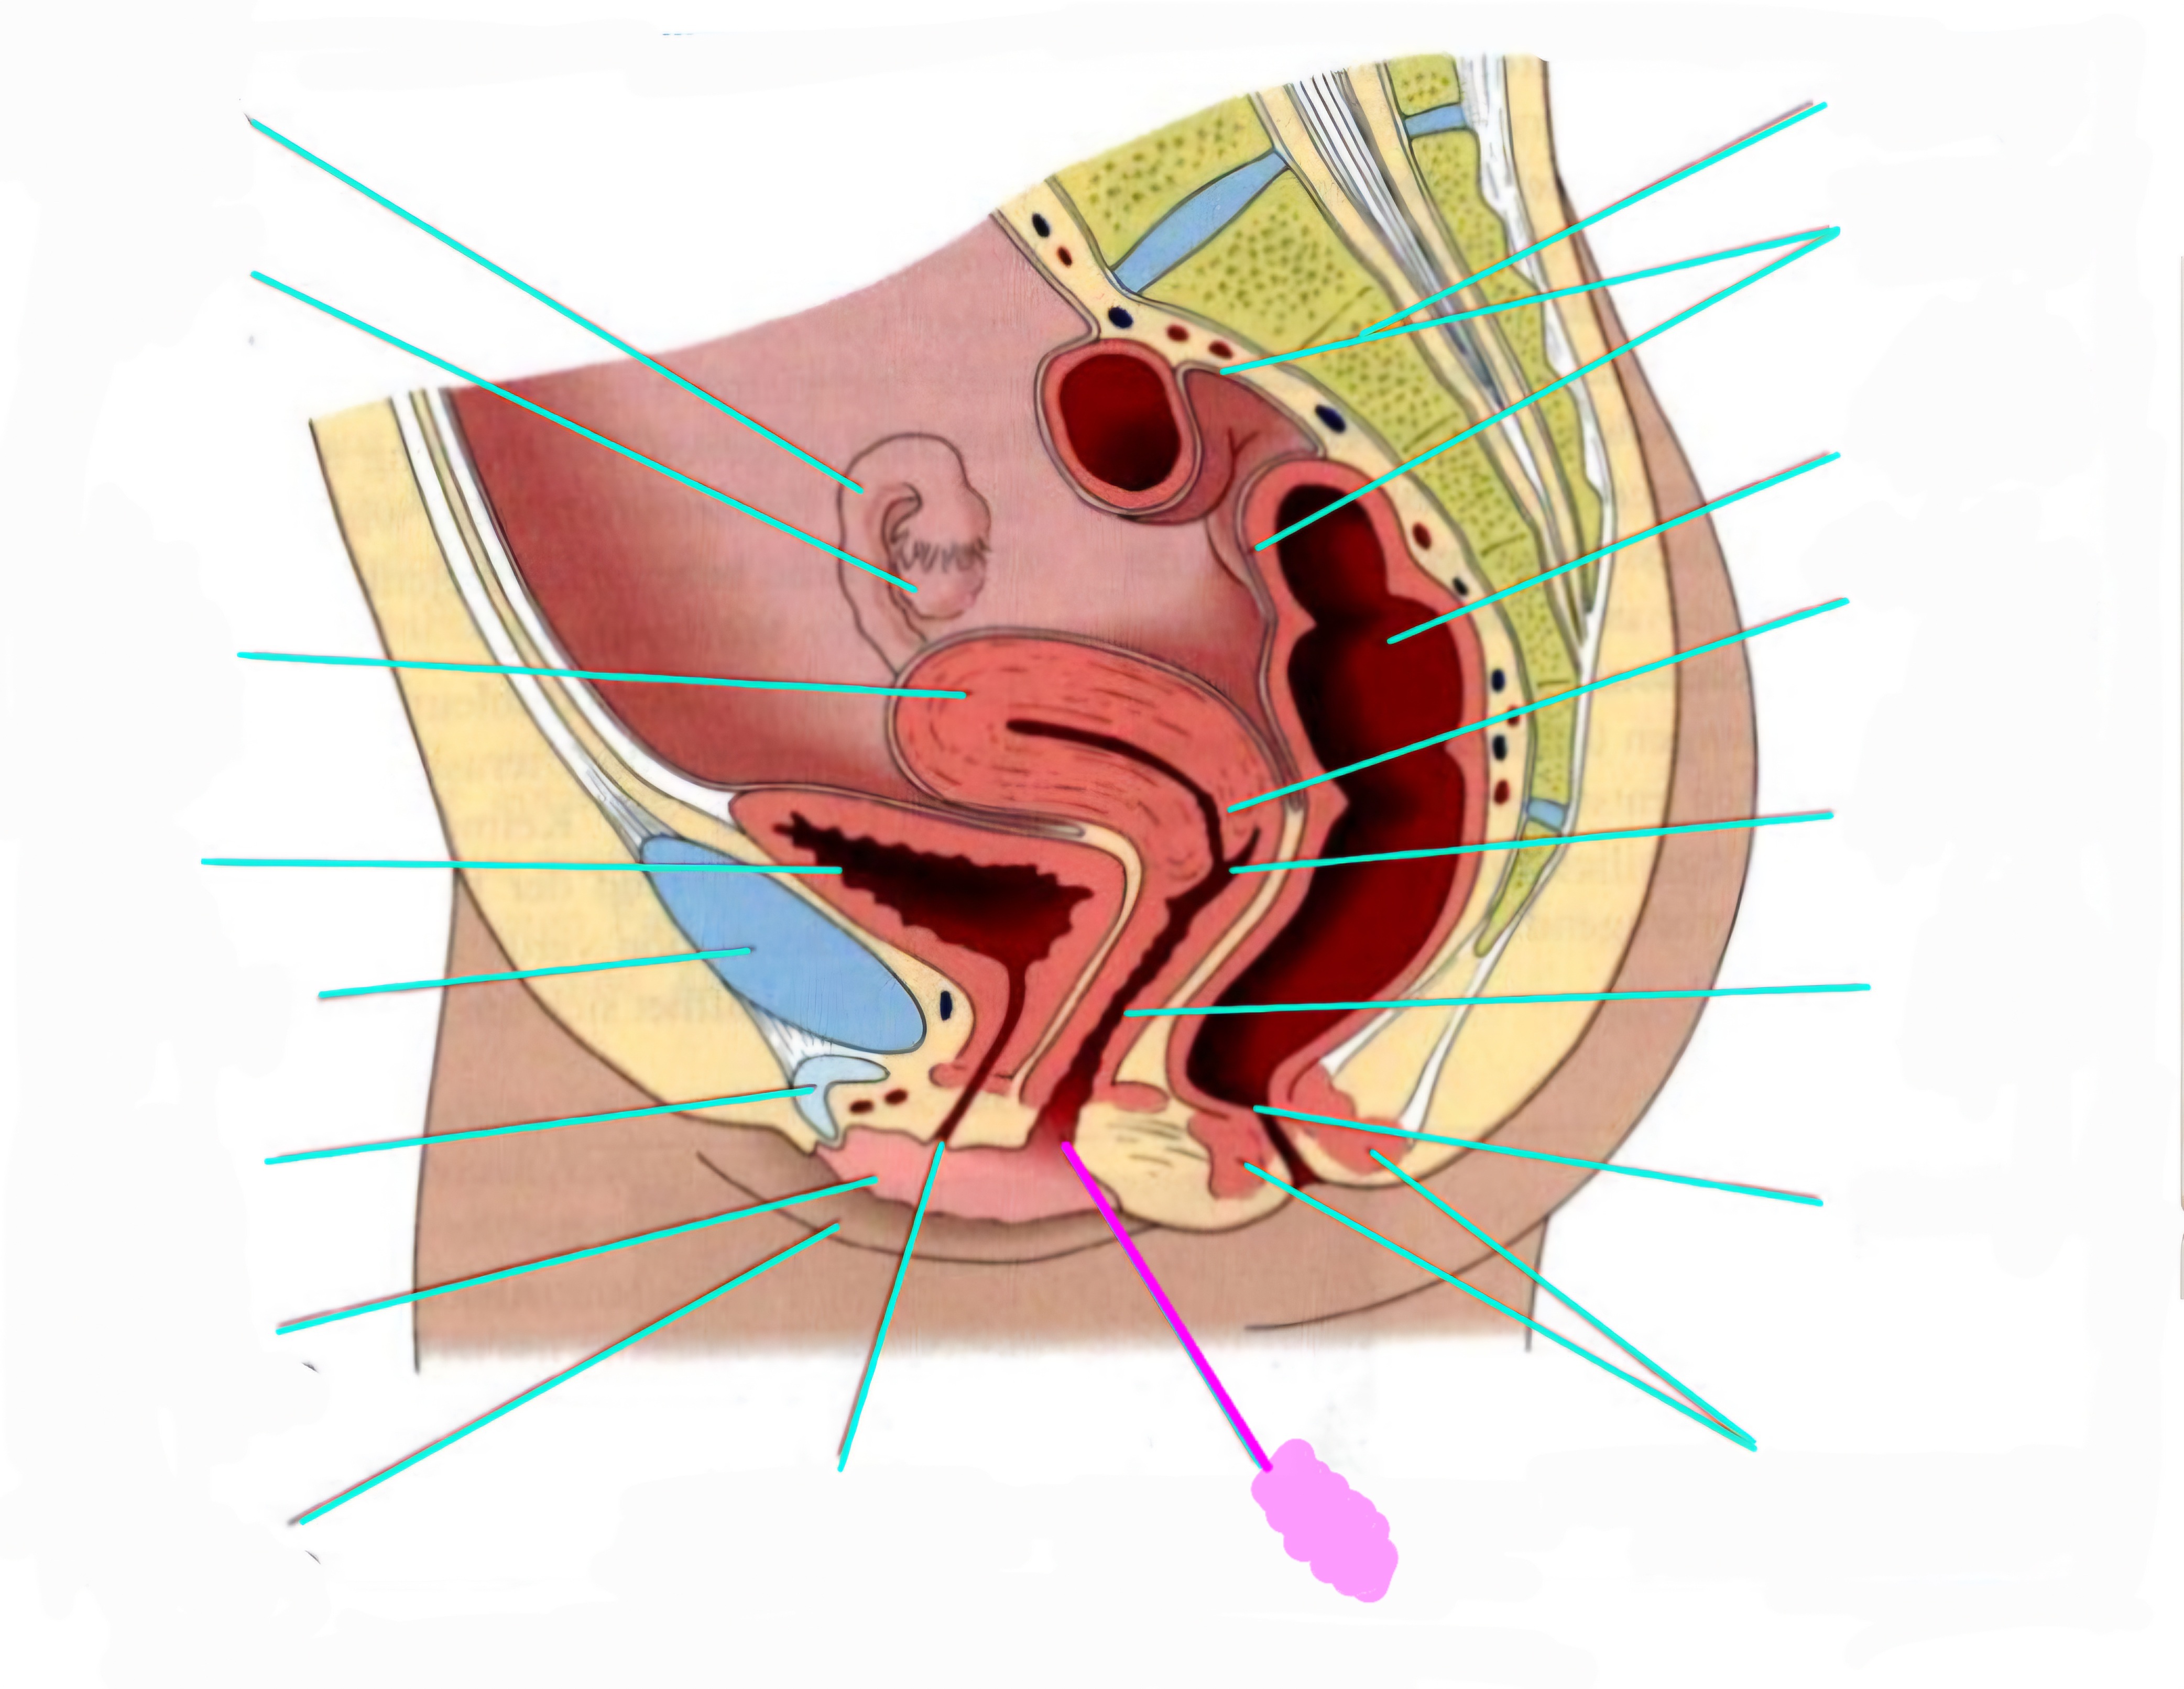

wbl. genital Anatomie

19 Terms

Tubea uterina (Eileiter)

Ovar (Eierstock)

Uterus (Gebärmutter)

Vesica Urinaria (Harnblase)

Symphyse

Klitoris

Labia minor pudendi (kleine schamlippen)

Labia Majoran pudendi (große Schamlippe)

Urethra (Harnröhre)

Introitus vaginae (Scheideneingang)

Sphincter ani externes (äußere Afterschließmuskel)

Anus (After)

Vagina (Scheide)

Portio (äußerer Muttermund)

Rektum (Mastdarm)

Zervix (Gebärmutterhals)

Peritoneum (Bauchfell)

Os sacrum (Kreuzbein)